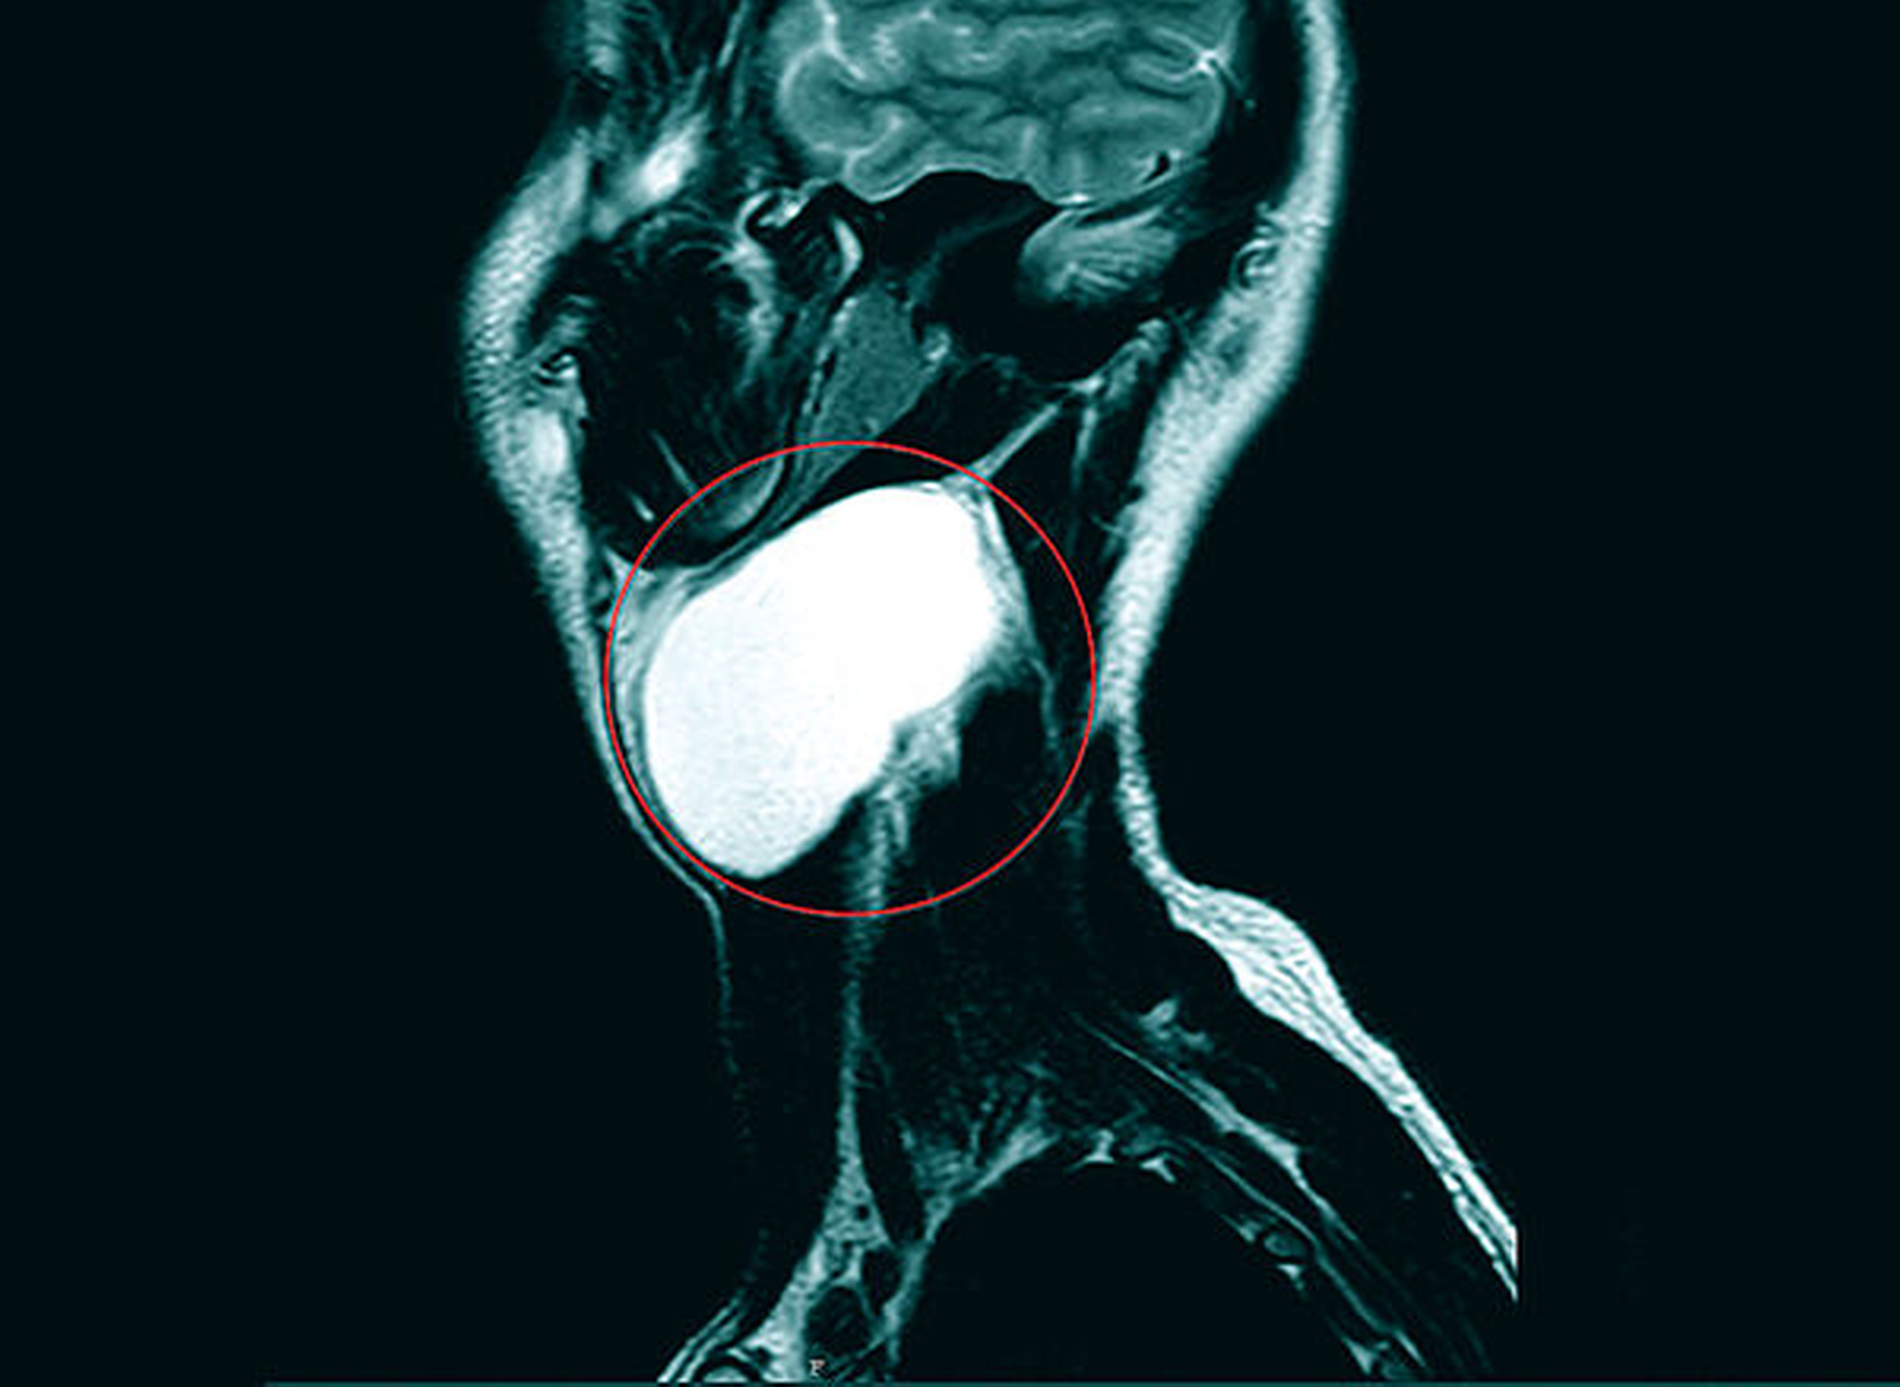

Zur weiteren Abklärung wurde eine Magnetresonanz-Untersuchung initiiert. Es zeigte sich eine glatt berandete, T2-hyperintense Raumforderung zervikal links auf Höhe der Epiglottis. Eine Infiltration der benachbarten Strukturen war nicht ersichtlich (Abbildungen 2 bis 4).